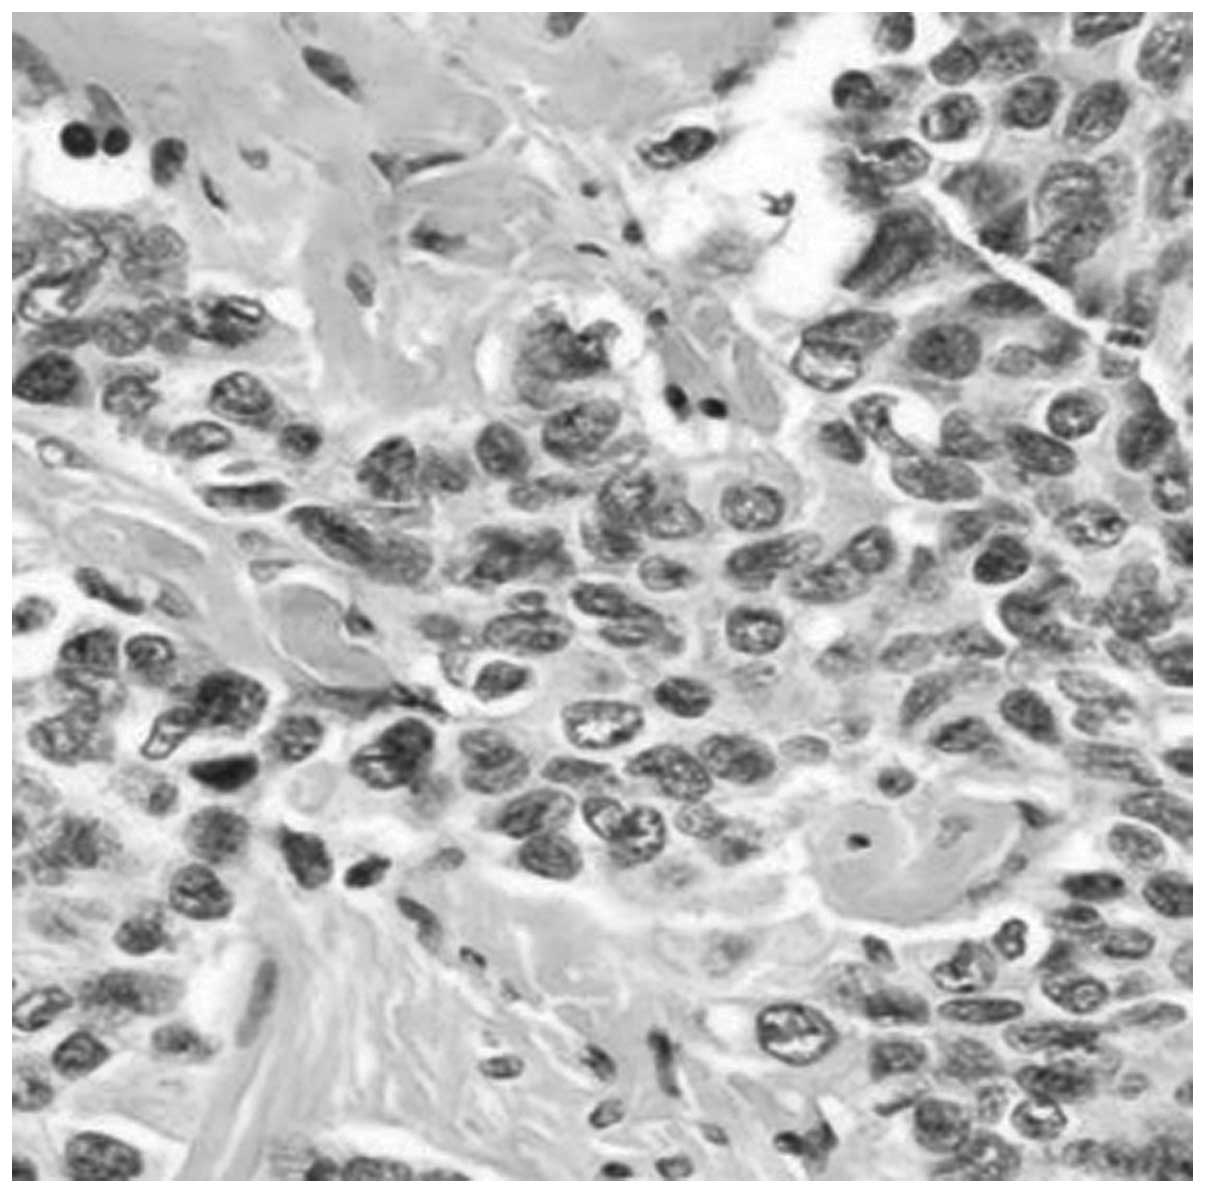

Primary desmoplastic small round cell tumor of the testis: A case report and review of the literature

Desmoplastic small round cell tumors (DSRCTs) are extremely rare and mainly affect adolescents and young adults. The tumors are usually involved with the abdominal area and/or the pelvic peritoneum. Only a small number of cases have been reported concerning DSRCTs of the testicular region. The present study reports a case of DSRCT of the testis with radical orchectomy and systemic chemotherapy, leaving the patient disease-free for 14 months. However, the patient died of multiple metastasis 12 months later. Furthermore there is a review of the English literature to analyze the incidence, site of origin, imaging and pathological characteristics of DSRCT.

Figure 1